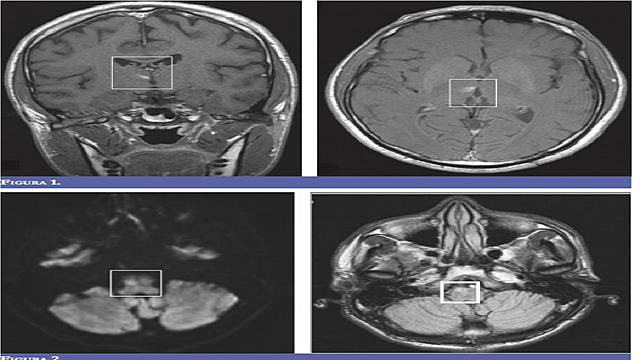

Resultados: glucometriá 272 mg/ dl, Hb Glicosilada 15,8%. La RM

del encéfalo: evidenció lesión que restringiá la difusión, visible en FLAIR y T2. Imagen hiperintensa en T1